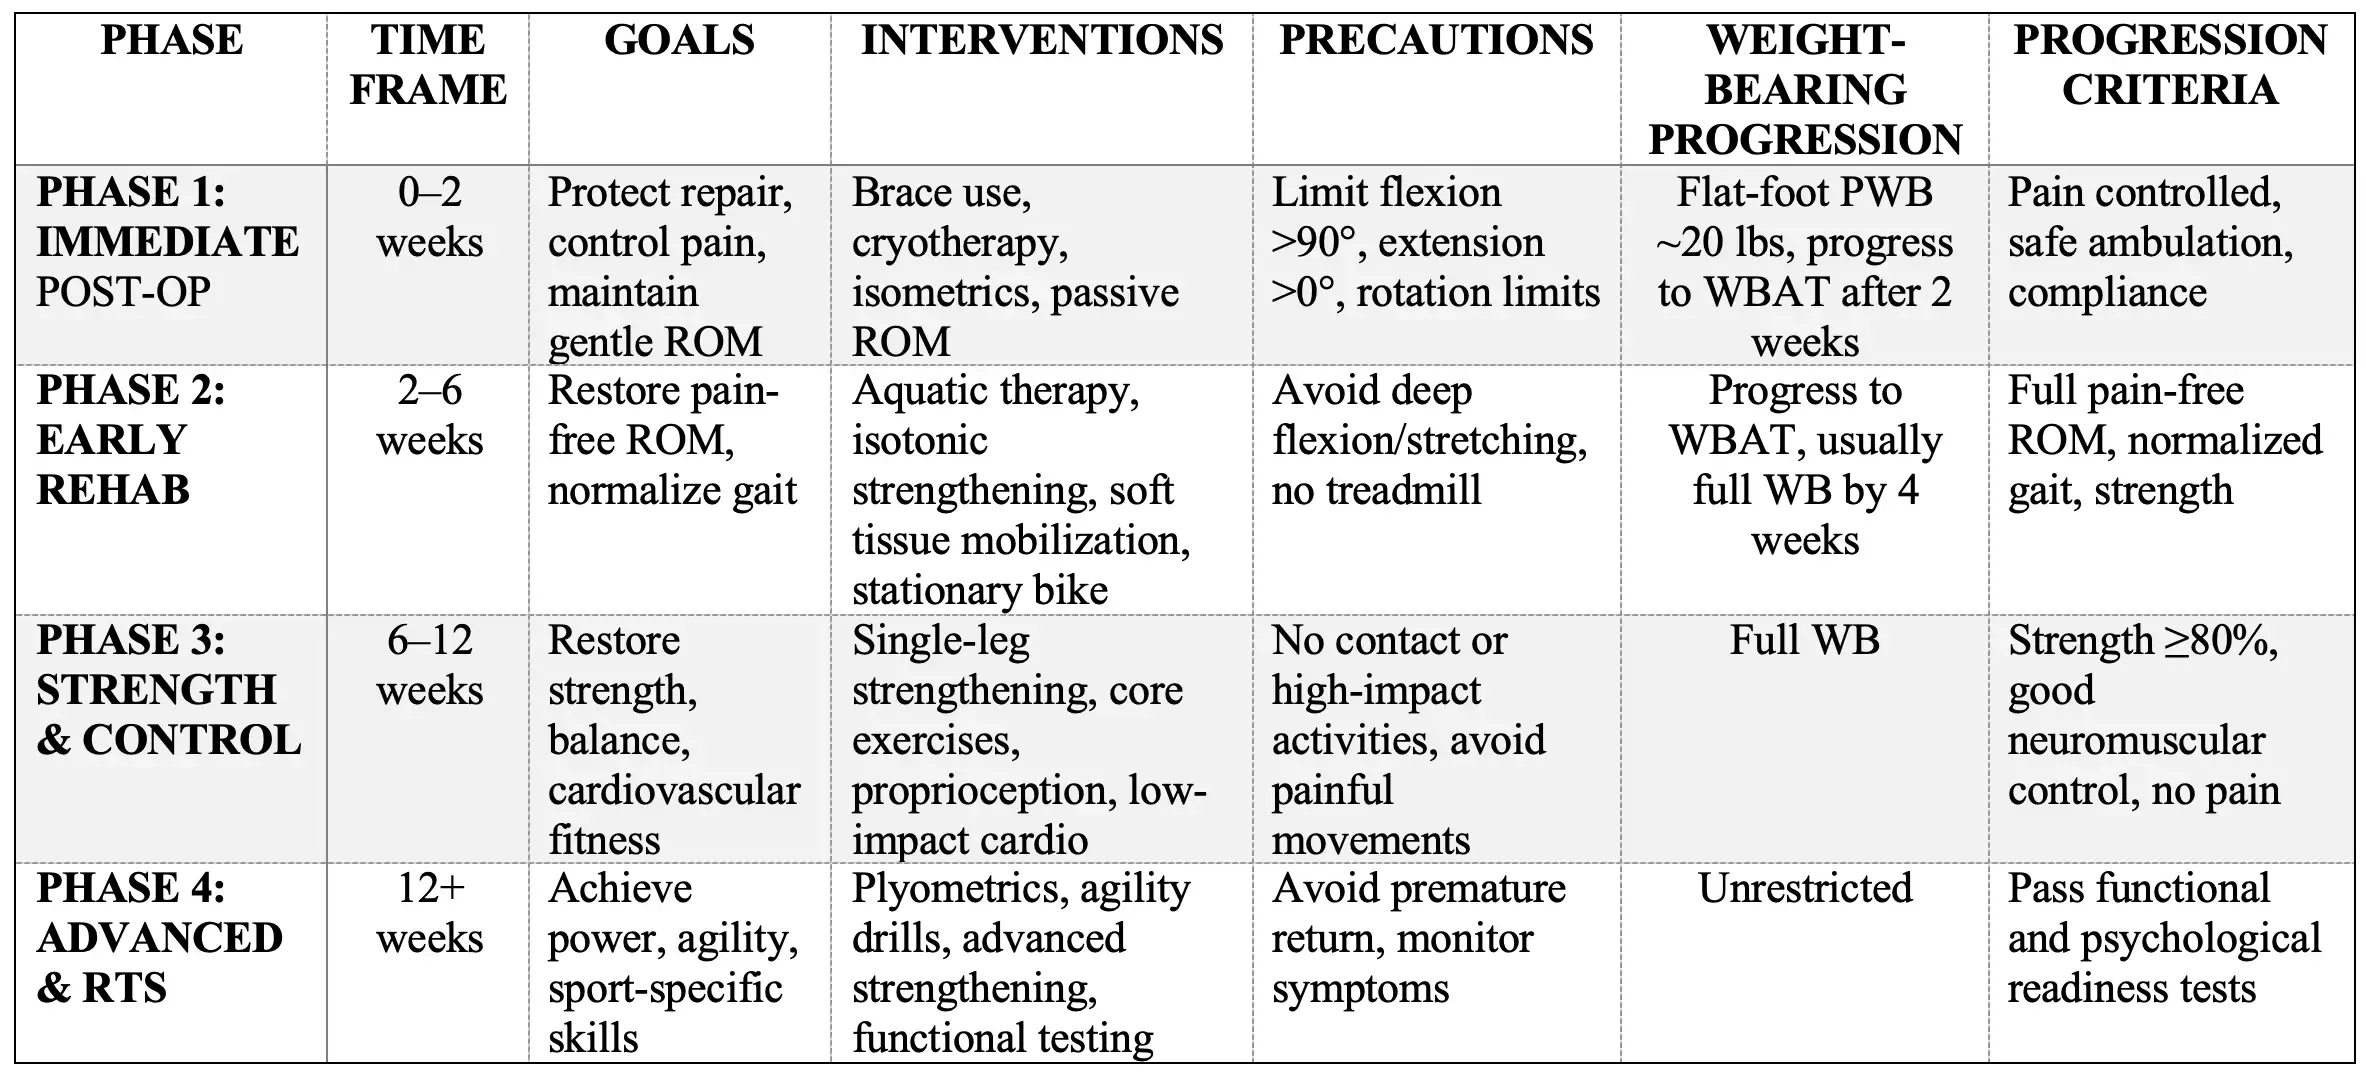

Summary Table of Rehabilitation Phases After Hip Arthroscopy

Phase 1: Immediate Post-Operative Phase (0–2 Weeks)

Goals:

- Protect surgical repair and promote healing

- Control pain and inflammation

- Prevent muscle inhibition and atrophy

- Maintain gentle range of motion (ROM) within safe limits

- Educate patient on precautions and safe mobility

Interventions:

Phase 2: Early Rehabilitation Phase (2–6 Weeks)

Goals:

- Restore pain-free full or functional ROM

- Normalize gait pattern without assistive devices

- Begin gentle strengthening focusing on neuromuscular control

- Prevent muscle atrophy and adhesions

Phase 3: Strengthening and Neuromuscular Control Phase (6–12 Weeks)

Goals:

- Restore hip muscle strength, especially abductors, extensors, and rotators

- Improve dynamic balance and neuromuscular control

- Enhance cardiovascular endurance

- Begin gradual return to functional activities

Phase 4: Advanced Functional and Return to Sport Phase (12+ Weeks)

Goals:

- Achieve pre-injury or better hip strength and endurance

- Enhance power, agility, and sport-specific skills

- Ensure psychological readiness for return to activity